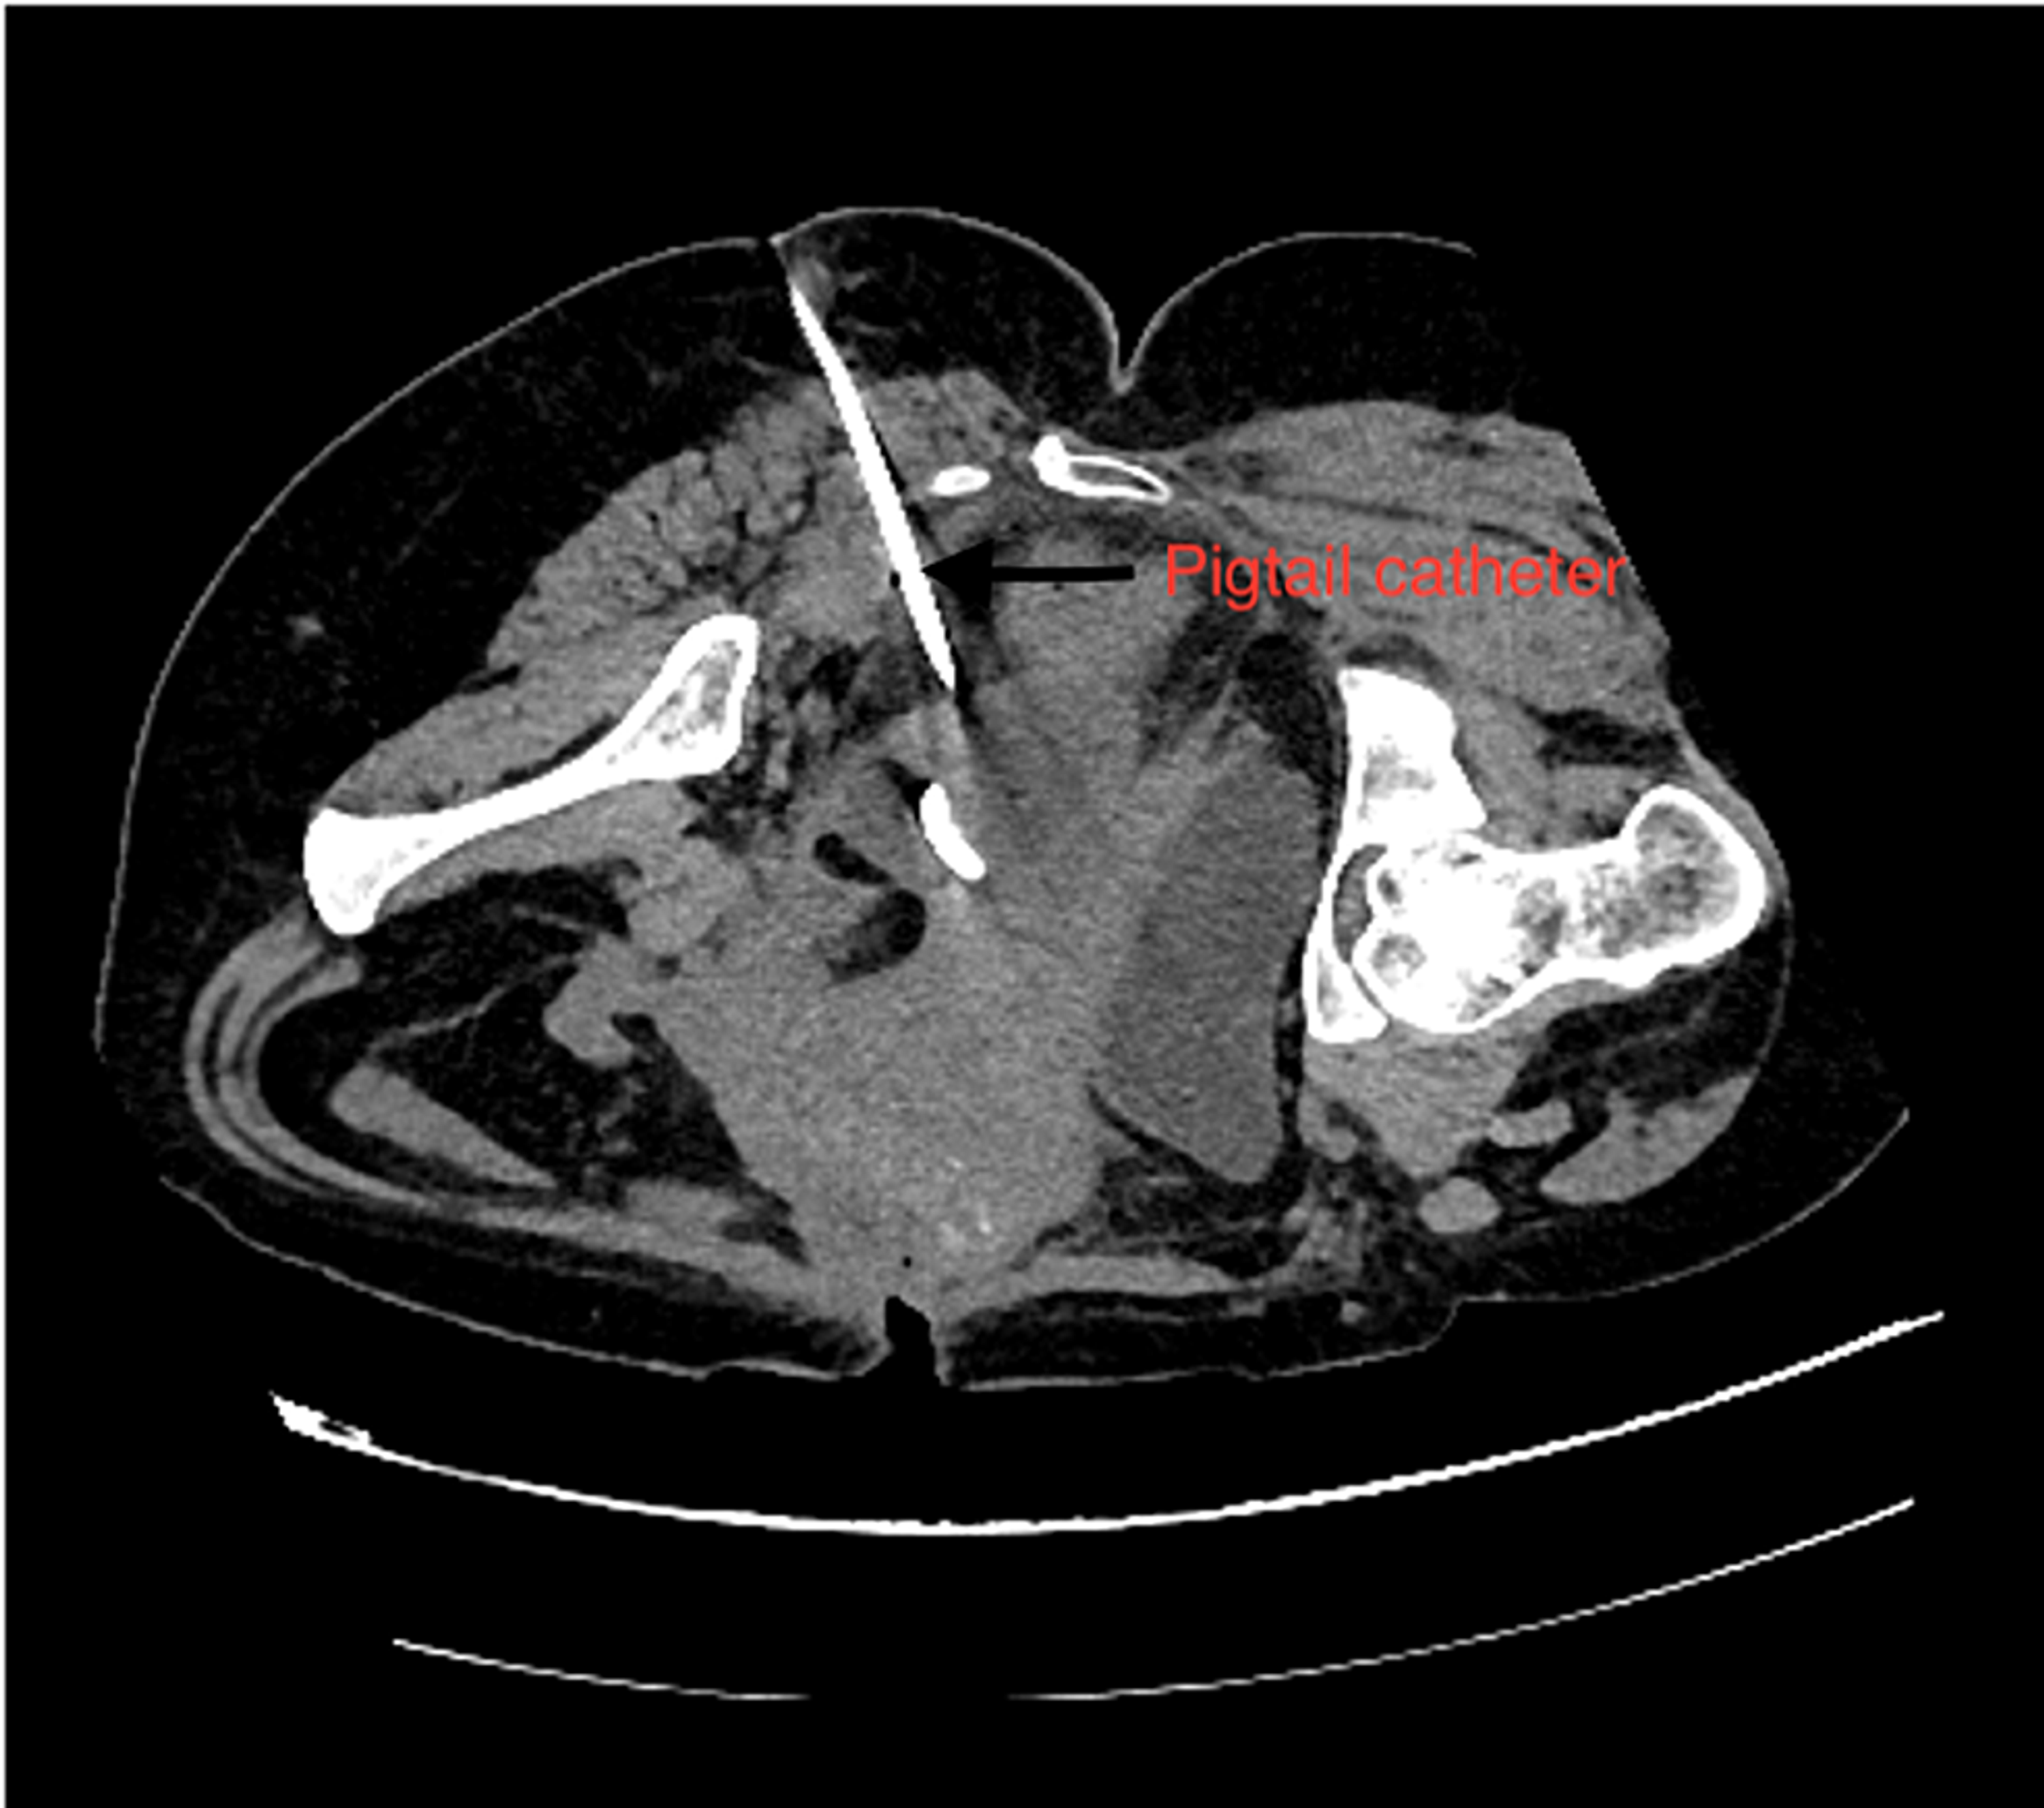

Cureus Post Caesarean Section Deep Pelvic Abscess CT Guided Ct Scan Drainage Deep pelvic abscesses may present a unique challenge for percutaneous drainage because of numerous overlying structures, which preclude safe percutaneous. In percutaneous abscess drainage, an interventional radiologist uses imaging guidance (ct, ultrasound or fluoroscopy) to place a thin. In cases in which fistula is suspected the injection of diluted contrast media in the drainage and an additional post. Ct and. Ct Scan Drainage.

CTguided Transgluteal Drainage of Deep Pelvic Abscesses Indications Ct Scan Drainage Deep pelvic abscesses may present a unique challenge for percutaneous drainage because of numerous overlying structures, which preclude safe percutaneous. In cases in which fistula is suspected the injection of diluted contrast media in the drainage and an additional post. Ct and less commonly mri and us are used to diagnose suspected mesh complications. In percutaneous abscess drainage, an interventional. Ct Scan Drainage.

CTguided Transgluteal Drainage of Deep Pelvic Abscesses Indications Ct Scan Drainage Ct and less commonly mri and us are used to diagnose suspected mesh complications. In percutaneous abscess drainage, an interventional radiologist uses imaging guidance (ct, ultrasound or fluoroscopy) to place a thin. Deep pelvic abscesses may present a unique challenge for percutaneous drainage because of numerous overlying structures, which preclude safe percutaneous. In cases in which fistula is suspected the. Ct Scan Drainage.